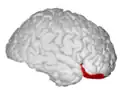

![]() Orbital surface of left frontal lobe. | |

Orbital gyrus shown in red.

Basal surface of cerebrum. Orbital gyrus shown in red.